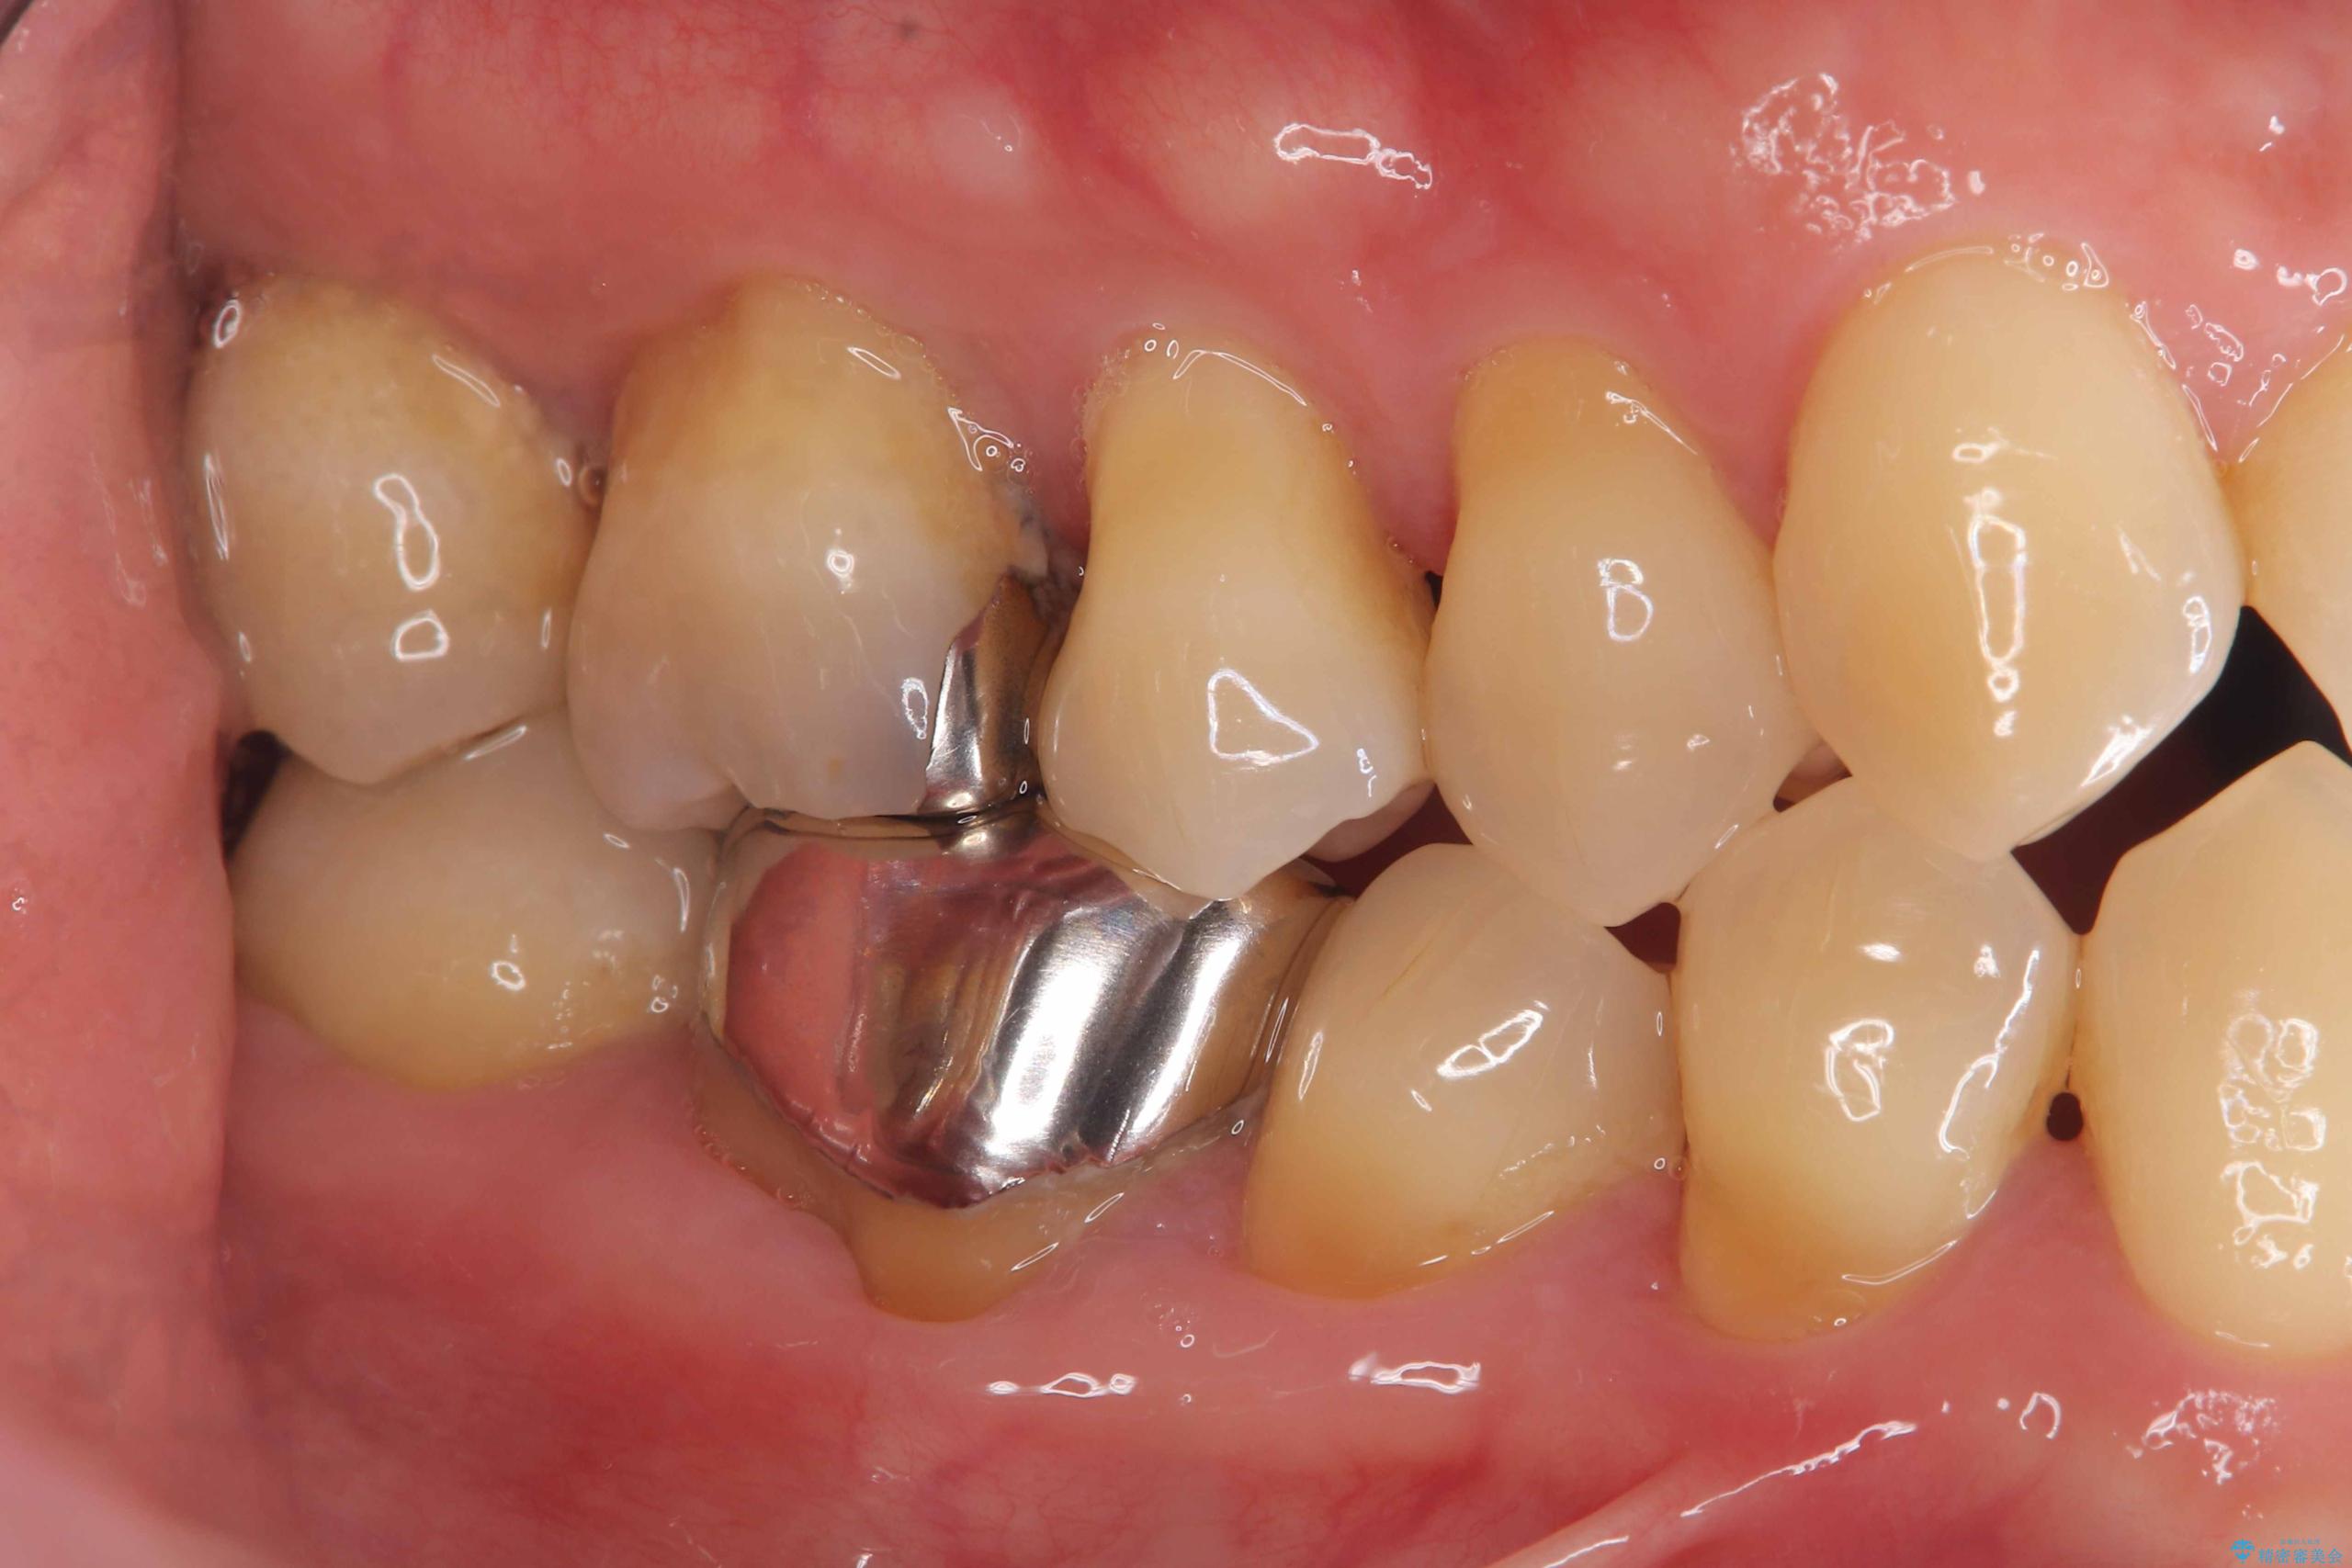

- 「銀歯を白くしたい」を主訴に来院された患者様です。銀歯を外し虫歯を除去後、オールセラミッククラウンで治療を行いました。

銀歯を外して内部の虫歯を丁寧に除去した後、オールセラミッククラウンにて修復を行いました。審美性と機能性の両面で改善が得られ、患者様にもご満足いただきました。